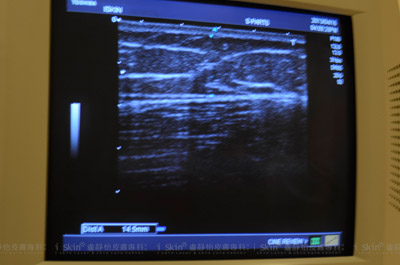

▲另外也可透過超音波儀器的檢測讓盧靜怡院長精準的判別治療部位脂肪層的厚度。

▲酷爾塑平前超音波儀器檢測脂肪層厚度